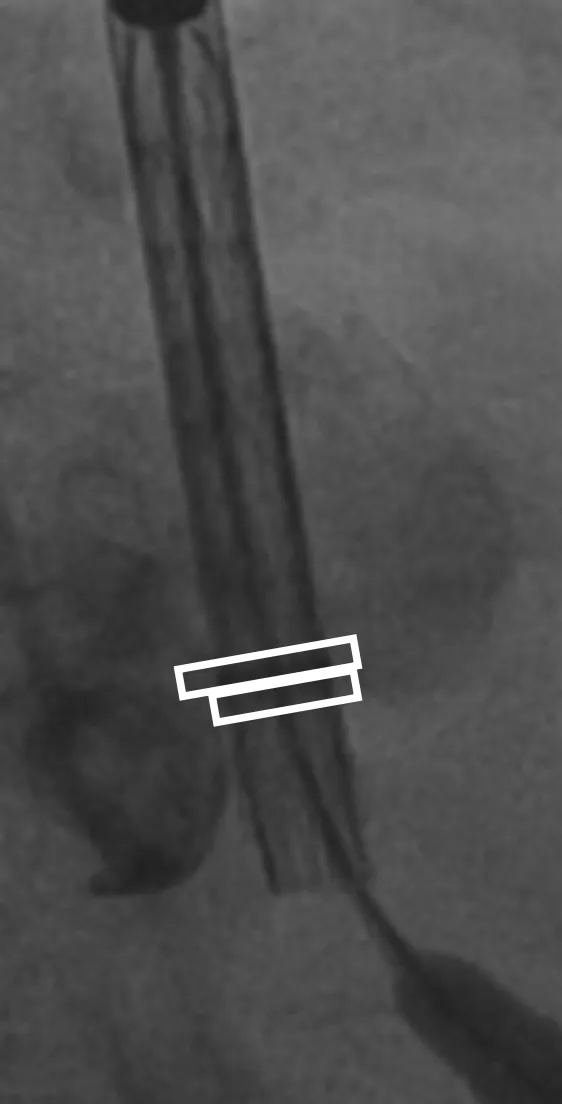

病例概览

患者病史 男性,74y, 因 “发现心脏瓣膜病 1 年,加重伴喘气半年” 入院。门诊检查显示主动脉瓣重度AS并伴轻-中度AR。患者基础疾病较多:胸腹主动脉多发穿透性溃疡、心功能III级等,手术指征明确,但风险极高。 术前CT LVOT- Annulus 倒梯形,对植入瓣膜有挤压位移风险,Annulus直径23.7mm,瓣叶增厚,钙化集中在无冠窦边缘。 左冠脉开口高度可,瓣叶不长、窦部空间较大,无冠脉风险;室间隔膜部较短,有一定PPI风险,心脏角度37.9°;心室较小,有一定循环崩溃风险,术前注意补液。 术前造影角度及入路:血管入路散在钙化、无迂曲;主动脉弓条件好、双侧股动脉直径大、右股穿刺点侧壁存在环形钙化 左右重合位:RAO 7° CAU 21° 右窦中心位:LAO2 1° CAU 1° 手术策略 20mm球囊预扩后植入AV26瓣膜,同时做好预防循环崩溃、传导阻滞的应急预案。 术中挑战 1)球囊预扩:20mm球囊预扩时无明显 “腰征”,但存在少量反流,提示瓣膜钙化与解剖结构对扩张的阻力不均 2)首次释放偏差:第一次定位释放时,瓣膜在 “开花” 过程中下滑约 3mm,工作位观察显示小弯侧瓣周漏较多(深度超过完全覆膜区),需二次调整。 3)二次精准定位:以猪尾导管为参照,将定位点调整至 “猪尾 - 2mm” 处,结合真实窦底深度(较深)重新释放,最终瓣膜位置稳定,瓣周漏显著减少。 术后即刻效果: 瓣膜形态良好,跨瓣压差从术前的 67mmHg 降至 6mmHg,且无明显瓣周漏,冠脉开口通畅; Commisural Alignment 术后即刻超声: Prostyle A®预装干瓣——助力临床最优化解决方案: √ 平衡的径向支撑力:特殊的解剖结构下位置形态良好,术后跨瓣压差大幅降低,血流动力学改善明显; √ 80%可回收设计:支持术中二次调整释放位置,保证精准释放; √ 平衡的收腰设计&Commissural Alignment设计: 为患者后期冠脉PCI保留了生命通道;